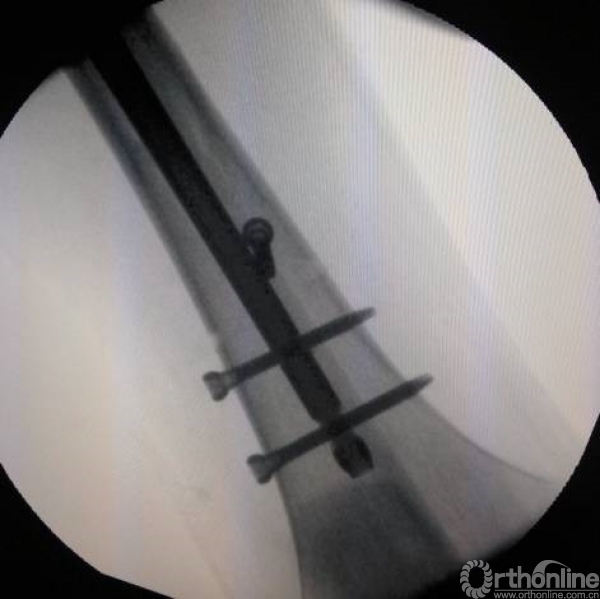

或采用钳加复位,复位之后可以较好的植入头钉。

牵引钳加复位后。

微创钳加复位。